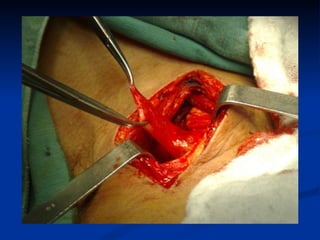

El documento habla sobre la anatomía y trastornos del esófago. Menciona las condiciones como el esófago de Barrett, el divertículo de Zencker, la acalasia y el cáncer de esófago, describiendo sus síntomas y tratamientos. Explica que el esófago de Barrett aumenta el riesgo de cáncer esofágico y que la acalasia se caracteriza por la hipertrofia del esfínter esofágico inferior y la ausencia de peristaltismo. También cubre factores de riesgo